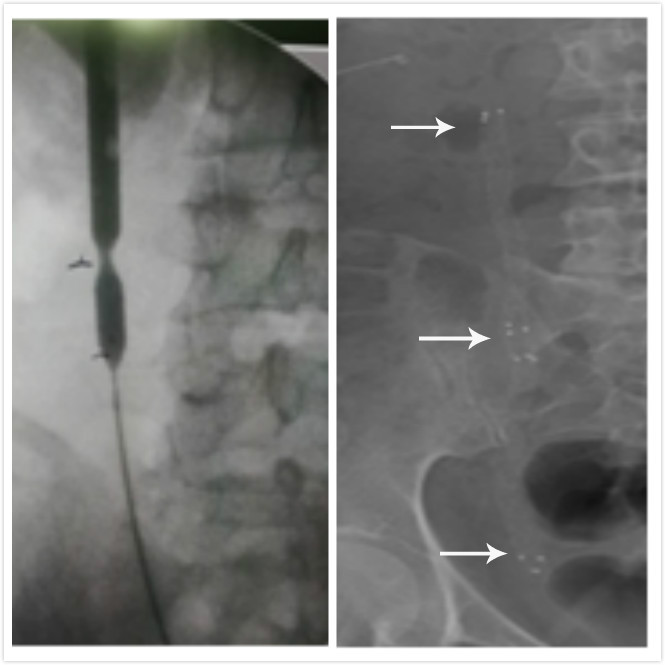

覆膜支架是目前治疗输尿管狭窄的新技术,它是一种自膨胀大口径支架,由镍钛合金制成,该支架由一层薄的聚合物所覆盖,使它成为一个不渗漏的管道,以防止组织内生长和早期结垢,是目前世界上先进的支架。近日,燕达医院泌尿外科引入覆膜支架技术,成功为一位患者实施了输尿管球囊扩张+输尿管覆膜支架管置入手术为患者解除了多年的病痛。

泌尿外科张鹏主任详细了解患者病史后,立即带领科室全体成员讨论研究,并确定覆膜支架为其治疗手段。经过严谨评估和精细准备,近日,张鹏主任亲自主导为冯先生实施了全麻下完成了输尿管球囊扩张+输尿管覆膜支架管置入手术。术后,冯先生恢复良好,膀胱刺激症状明显减轻。